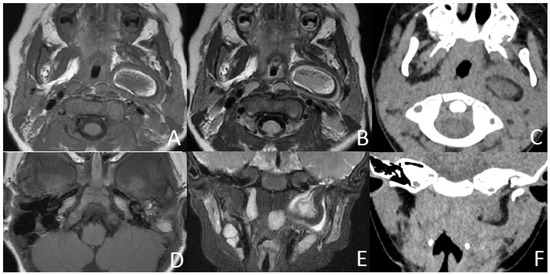

Figure 6. CT of a 2-year and 11-month boy presenting with snoring and mouth breathing for 3 months and hearing impairment found during physical examination. (A,B) Axial and coronal CT displayed in the soft-tissue window show the fat density mass (long arrow) originating from the back side of the left soft palate with a soft tissue density core (short arrow). (C) Axial CT, displayed in the bone window, shows the absence of the left stapes head and part of the stapes arch (arrow).

The size of masses varied from 0.6 to 4.3 cm. There were 11 (78.6%) cases with the largest diameter of the mass greater than 2 cm. The shapes of the masses were varied. Eleven (78.6%) cases presented with typical pedicled masses containing fat and a central core of soft tissue, including sausage-like masses in five (35.7%) cases, tongue-like masses in four (28.6%) cases, and pear-like masses in two (14.3%) cases. Of the eight patients who underwent MRI scans, there were five (62.5%) patients whose masses had high signal intensity on T1-weighted and T2-weighted sequences with a low-signal central core whose signal intensities were similar to those of muscles. The high signal intensities on all sequences were similar to the fat signals and attenuated by fat suppression. The central core demonstrated mild enhancement following intravenous gadolinium administration, while the surrounding components of the fat signals demonstrated no enhancement in one case (Figure 1). There was no reduced diffusion of the five patients who underwent DWI. Via CT, there were 10 (83.3%) cases whose masses appeared as well-circumscribed fat attenuation masses surrounding a central core of soft tissue. The central core was mildly enhanced following intravenous iodixanol administration, but the fat components were not enhanced in one case (Figure 2). There were five patients who received both MRI and CT.

3.3. Associated Malformation

Upon MRI, most of the masses were found to have heterogeneous high signal intensity on T1-weighted and T2-weighted sequences with a low-signal central core whose signal intensities were similar to those of muscles. The high signal intensities on all sequences were similar to the fat signals and attenuated by fat suppression. The central core demonstrated mild enhancement following intravenous gadolinium administration, while the surrounding components of the fat signals demonstrated no enhancement. The central core helps us trace the origin of the mass, which is important for the choice of surgical method. Characteristic imaging features on CT include well-circumscribed masses containing fat and linear soft tissue–density components centrally that correspond to the fibrovascular stalk [2]. The central core was mildly enhanced, as expected for fibrous tissue, but the fat components were not [23]. These findings corresponded well with the MRI and CT features previously described [24,25]. Intracranial or intraspinal extension was not found in any of the lesions in the present study, which was consistent with existing reports.